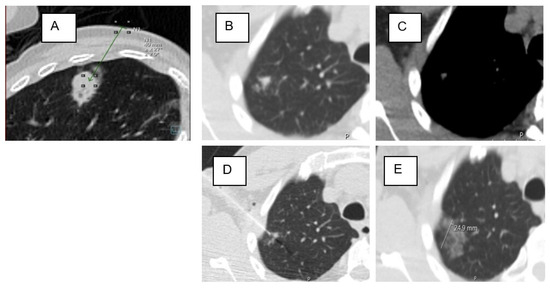

| Lesion location in D area | 53 | 46% | 34 | 40% | 19 | 63% | 0.034 * |

| Lesion location in D area | 1.402 | 0.517 | 7.369 | 1 | 0.007 * | 4.064 | 1.477 | 11.186 |